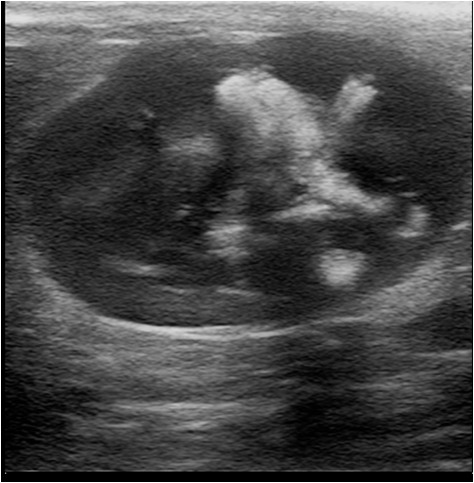

Kystes ovariens des cobayes

Les kystes ovariens sont très fréquents chez les femelles cobayes et gerbilles. La grande majorité du temps, ils sont totalement asymptomatiques. Mais parfois, du fait de leur taille, ils peuvent comprimer les organes abdominaux. Lorsqu'ils sécrètent des hormones, les kystes ovariens peuvent occasionner des pertes de poils importantes ou des tumeurs mammaires et utérines.

Le diagnostic se fait par échographie. Le traitement est chirurgical. Une technique d'ovariectomie par les flancs est généralement préférée en l'absence de tumeur utérine, elle est de bon pronostic.